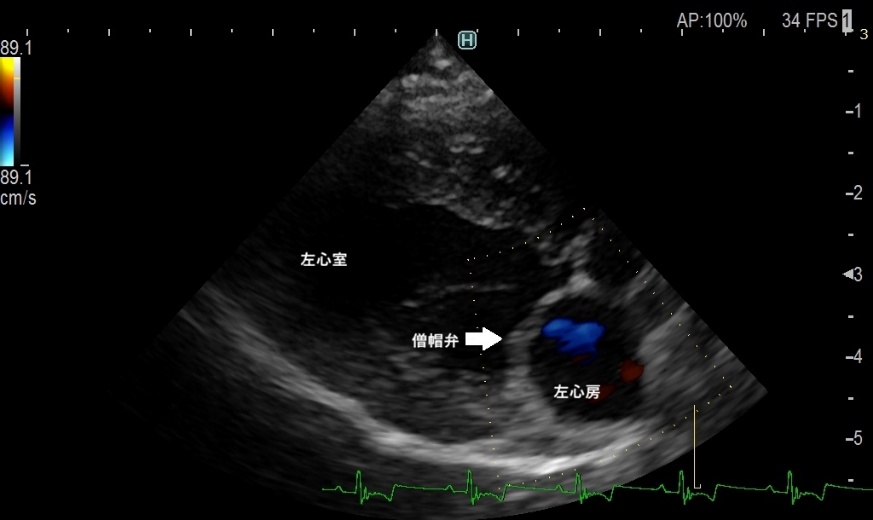

心臓は4つの部屋に分かれていますが、そのうちの左心房と左心室を隔てているのが「僧帽弁」で、血液の逆流を防いでいます。本来薄い僧帽弁の先端が腫れてしまう「粘液腫様変性」と呼ばれる変化が起きると、弁がうまく閉じなくなり、左心房から左心室へ流れるはずの血液の一部が左心房へ逆流します。この僧帽弁逆流は、聴診器で聞き取ることができます。